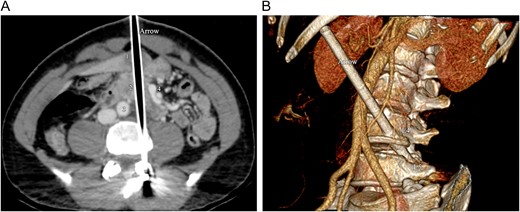

Intravenous contrast-enhanced CT of the abdomen. (A) Axial CT image shows the arrow, tracking through the liver (1), the pancreas (2) and the duodenum, between the aorta (3) and the superior mesenteric vessels (4). (B) 3D volume rendering CT reformation shows the oblique trajectory of the arrow, between the aorta (1) and the superior mesenteric artery (2). The arrow passes through the lateral aspect of the fourth vertebral lumbar body (L4) and ends into the left pedicle of the fifth lumbar vertebra (L5).

Such a CT assessment is of special interest in injuries caused by arrows, such as the one of our patient. Imaging allows a precise visualization of the arrow trajectory, and enables to build detailed 3D reconstructions, which is not the case with bullet injuries.